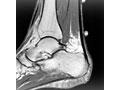

• MRI scan. It may be used to check the tendon for signs of tendinopathy or a tendon tear. An MRI is also used to evaluate the heel bone.